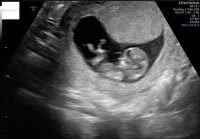

Her ble det positiv test 2 dager før året var omme.

Termin 17. september :O

Tusen takkGratulerer med en liten jente på vei og at du har kommet til uke 20![]()